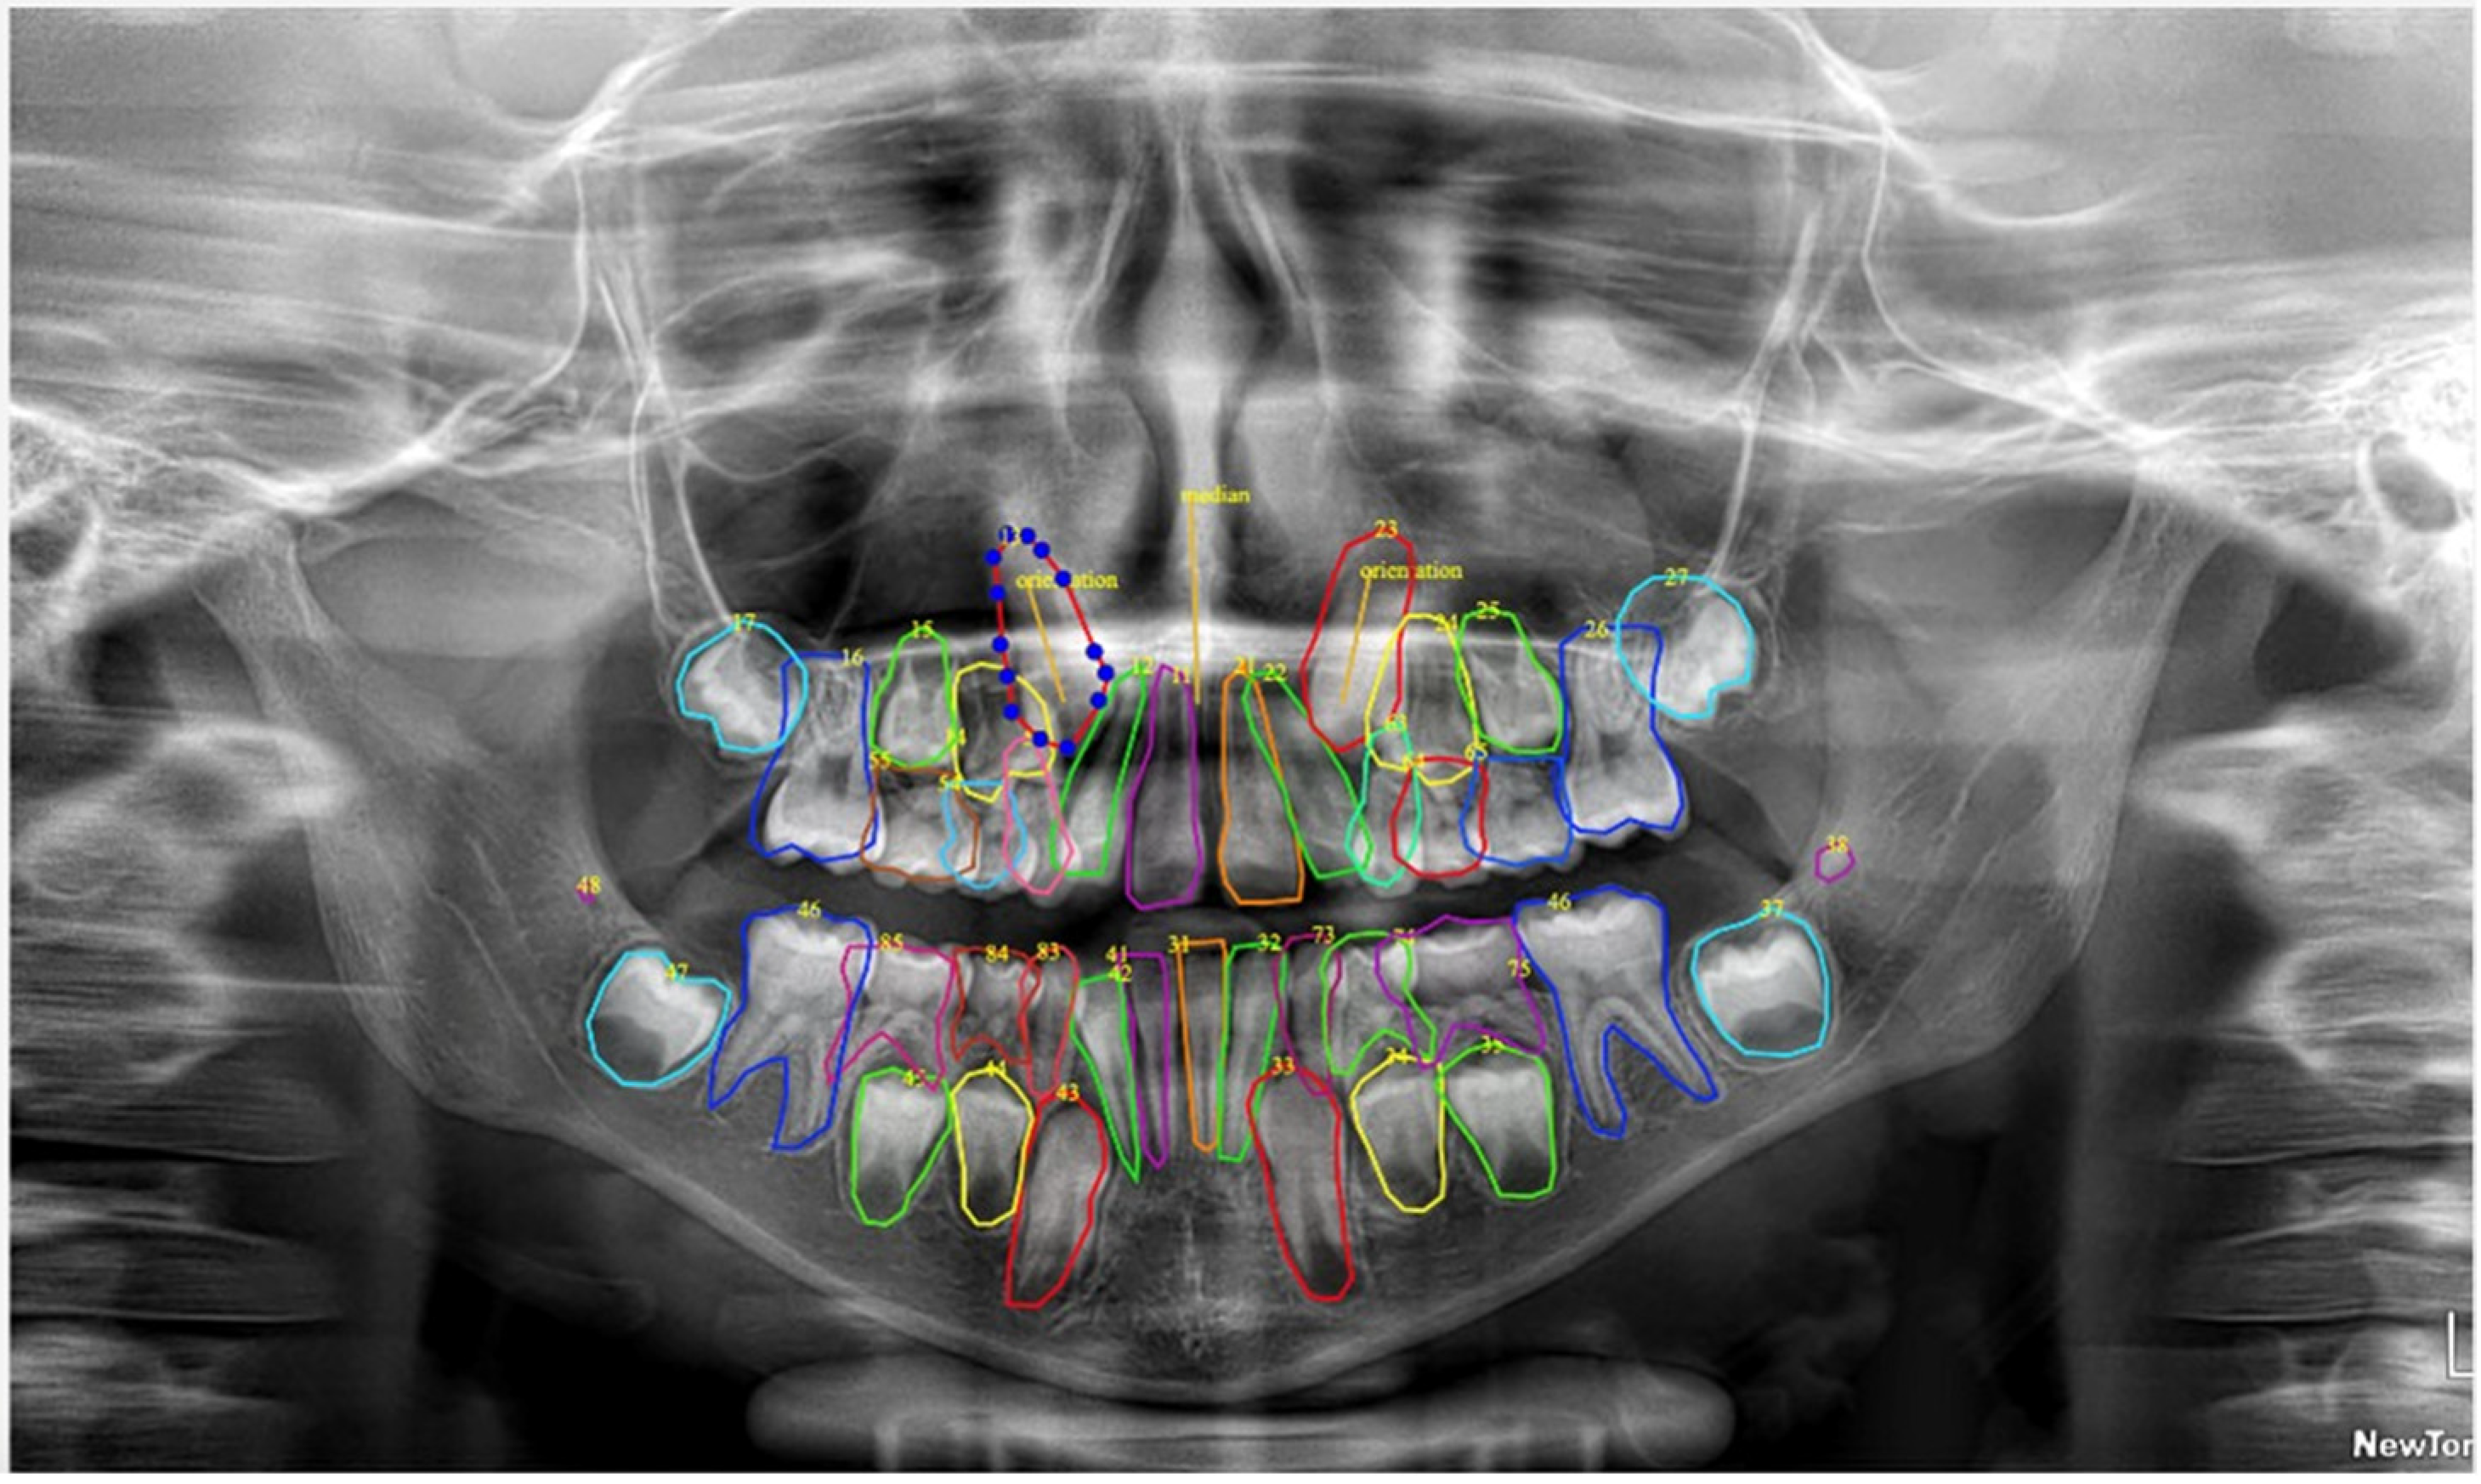

- detect the location of each object (in our case, each tooth),

- classify the object (e.g., tooth 11, tooth 12, tooth 35, etc.), and

- segment its precise contour (tooth boundary).

- bounding box coordinates (x, y, width, height),

- class label (e.g., 11, 12, …), and

- an instance-specific segmentation mask.